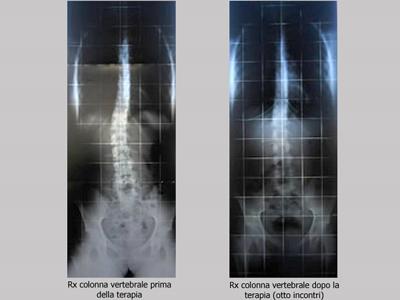

La muscolatura antigravitazionale, meno contratta per vincere la forza di gravità, schiaccerà meno lo scheletro e soprattutto la colonna vertebrale, che si potrà così distendere nello spazio, risolvendo in maniera definitiva patologie come cifosi dorsali, lordosi lombari e verticalizzazioni cervicali, e riducendo gli attriti che limitano il movimento e consumano muscoli, tendini ed articolazioni. Ma gli effetti della Fisioanalisi non si esauriscono qui: i muscoli più distesi schiacceranno meno anche tutti i tubi e le arterie di cui siamo costituiti, (vie arteriose e venose, vie digerenti, respiratorie, urinarie, linfatiche ecc.) nei quali si muovono i fluidi del corpo, e da cui ha origine buona parte delle patologie degenerative.

Questa tecnica è un mezzo efficace per ridurre il rischio di gravi malattie e prolungare gli anni di vita in maniera non ancora quantificabile, ma sicuramente molto significativa.